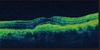

ERM

VMT with partial thickness macular hole